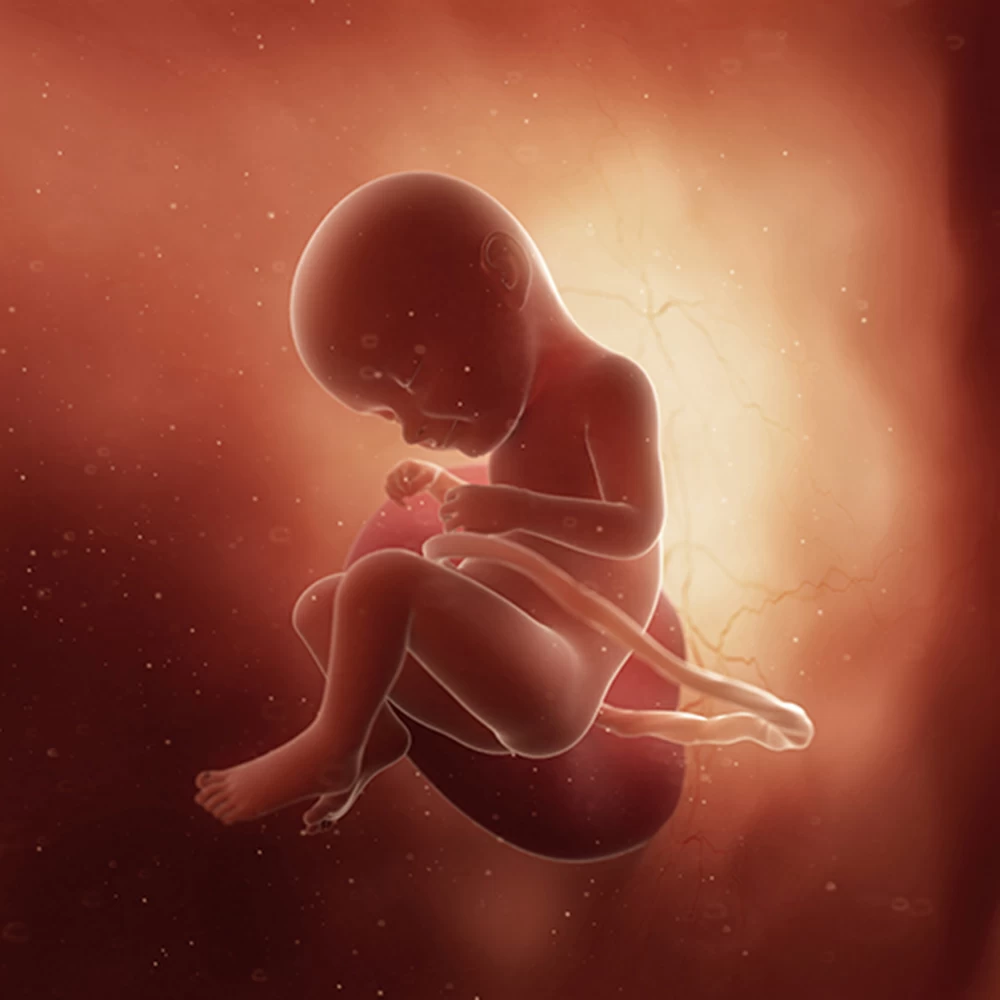

Нужна качественная и доступная медицинская помощь на протяжении всей беременности? Обращайтесь в нашу клинику! Мы гарантируем профессиональный подход к каждому пациенту и надежную медицинскую помощь. Нам важно индивидуальное отношение к каждому случаю, начиная с оплодотворения и заканчивая уходом за новорожденным. Вам не нужно переживать о цене услуг, мы придерживаемся гибкой ценовой политики и предоставляем доступные цены для всех клиентов. Доверьте свою беременность надежным специалистам!

Дневник беременности